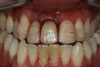

Providing single-tooth restorations in the smile zone can be challenging; considerations for implant dentistry for a single maxillary incisor can be even more challenging. For this case, the digital workflow considerations were not much different from the previous case; radiographs, photography, and analog impressions were used. The patient was given alternative treatment options. He chose a single implant and final zirconia with cutback for porcelain application. The patient was advised about his surrounding vintage dentistry and told he should consider all maxillary anterior teeth, Nos. 6 through 11, be planned for better function and esthetics. The patient had the final say, which allowed the laboratory and the author to finalize the treatment plan with the definitive restoration.

Figure 6 and Figure 7 depict a mature smile with many implant restorations. An analog impression was sent to the laboratory. The impression was scanned by the laboratory, a model was created virtually, and the implant dimensions and position were defined. The 3D surgical guide was fabricated (Figure 8), allowing the patient to receive his therapy swiftly and predictably. Tooth No. 8 was extracted, and the implant was placed and immediately loaded with an acrylic provisional treatment crown (Figure 9). The screw-retained treatment crown was fabricated in-office from a previously completed diagnostic wax-up.

Fig 6. Image of the patient’s mature smile.

Figure 6